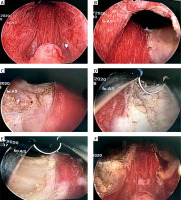

We found that the Qmax of the Experimental group and Control group significantly increased after surgery, and the IPSS and QOL scores notably decreased. The urination symptoms of the two groups were significantly improved after surgery. This shows that although we have preserved the prostate tissue at 5 to 7 loci, it does not affect the smooth urination of the patients. A survey conducted by Nadeem et al. [6] confirmed that transurethral incision of the prostate (TUIP) and TURP have the same effect in improving urination, suggesting that the residual prostate tissue does not affect urination function and the patient’s quality of life. Bladder neck mobility is closely associated with urinary incontinence [7]. Protecting the bladder neck can effectively reduce urinary incontinence. The reason may be the protection of the internal urethral sphincter. In the Control group, 1 patient had temporary urinary incontinence when the catheter was removed on the same day and recovered on the next day. However, the patients in the Experimental group did not have urinary incontinence. Therefore, our data suggest that keeping the bladder neck at 5 to 7 loci may reduce the incidence of urinary incontinence in patients (Photo 1).

Photo 1

Images of bladder neck in the Experimental group. A – Pre-operation. B – Removal of 5 loci of tissues. C – Removal of 7 loci of tissues. D – Smooth the 5 loci of incisional edge of the retained prostate tissue. E – Smooth the 7 loci of incisional edge of the retained prostate tissue. F – Post-operation